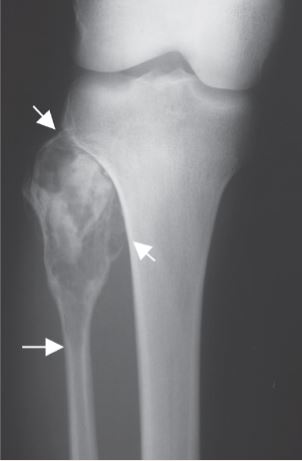

The compartment of the knee involves the tibia, fibula, patella, and distal femur bones. The fibula is a relatively small bone in comparison to the tibia (shin bone) and is a rare anatomic location for both primary and metastatic bone tumors. When a lesion does arise in this area, it typically occurs in the proximal fibula (part of bone closest to knee), followed by the diaphysis (middle part of bone), and finally the distal fibula (lower part of bone near ankle). The most common tumors to arise from the fibula, include chondrosarcoma, osteosarcoma, and benign aggressive cysts. Limb-sparing surgery can be performed for approximately 95% of tumors arising from the fibula. In some instances the extremity cannot be saved and an above the knee amputation is performed.

You will be monitored periodically with X-Ray and MRI imaging over the course of 5 years to ensure there are no signs of recurrence. You will have follow up appointments every 4 months for the first 2 years, then every 6 months for the next 2 years, and then once a year. Since the integrity of the limb has been restored to full or almost full, recovery is anticipated provided the patient adheres to strict physical therapy.